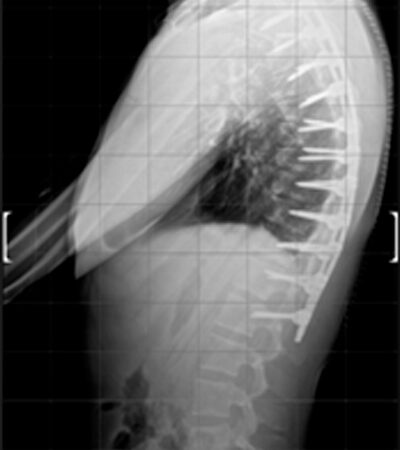

DIAGNOSI:

IPERCIFOSI DORSALE GRAVE

Radiografia dorsale pre operatoria

Intervento chirurgico eseguito:

STABILIZZAZIONE DORSO – LOMBARE CON OSTEOTOMIE CORRETTIVE

Radiografia dorsale post-operatoria